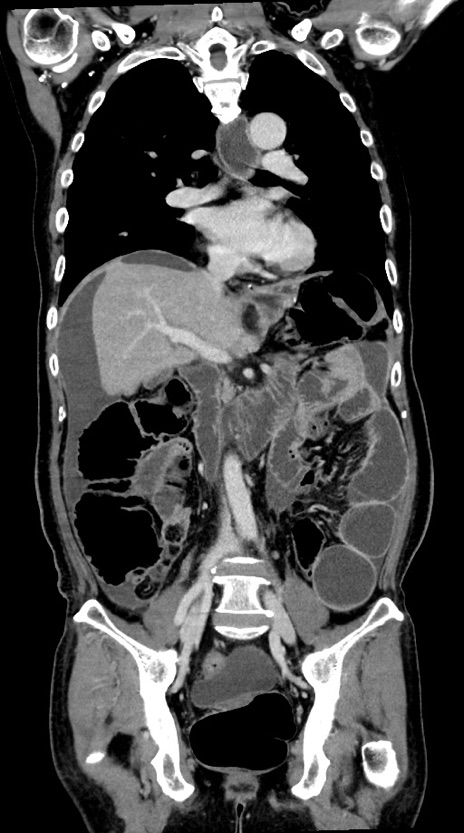

症例28(冠状断像)

【症例】60歳代男性

【主訴】嘔吐

【現病歴】胃癌にて胃全摘後。食思不振が悪化し、夜中に嘔吐することがある。

【既往歴】胃癌、胃全摘、脾摘、胆摘後

【データ】WBC 5900、CRP 10.56